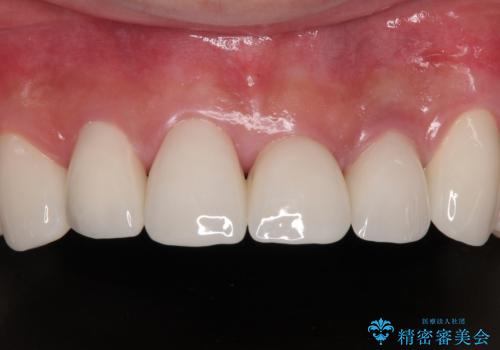

反対咬合を補綴治療で改善すると、上唇へ歯が当たる感覚や、発音時の舌感覚が急激に大きく変化するため、違和感になれるまで時間を要することになります。

仮歯で過ごす期間を一定期間も受けることで徐々に変化になれていくようにし、オールセラミッククラウン装着時には違和感なく過ごすことができるようにしています。